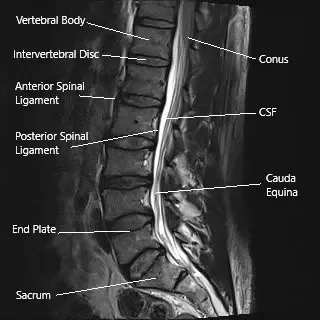

Sagittal section of the lumbar spine on an MRI.

The pain is due to a combination of inflammation and decreased blood supply to the nerve root commonly known as a nerve root irritation. The most common cause of this irritation is disc herniation. Other uncommon causes can be facet arthritis and synovial cyst.